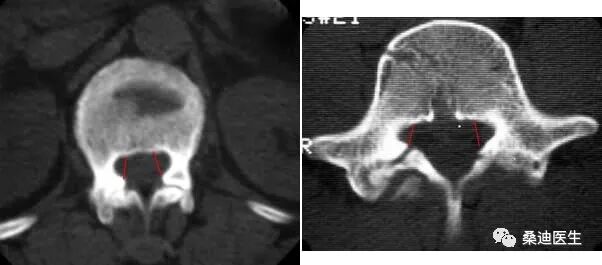

侧隐窝的测量必须满足两个条件:一是必须用骨窗位来测量,二是测量层面必须是完整的椎体层面,即显示出椎弓根的层面。

侧隐窝的测量方法是关节突的内侧缘与椎体后部的连线的长度:

侧隐窝宽窄的判断,小于3mm为肯定狭窄,3mm-5mm为可疑狭窄,大于5mm则不狭窄。